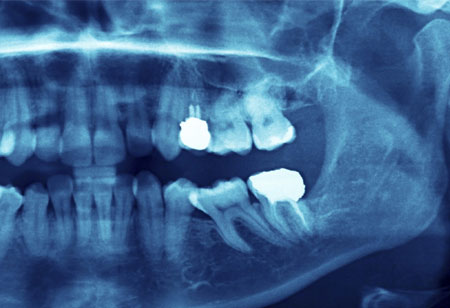

Medical Imaging becomes more Accurate and Easier with 3D X-Ray Techniques

The researchers may use the new approach to measure a 3D image before the sample can be destroyed which may be useful for delicate biological samples.

Today’s healthcare professionals have access to increasingly accurate images with which they can screen, diagnose, and guide patients through the advent of every modern imaging techniques–combined tomography, magnetic resonance imaging, ultrasound, and digital imaging. Medical images are a special type of images which can be used to diagnose patients’ diseases. There are several ways of obtaining these images, such as CT-scan, MRI, and X-ray imaging. Such types of imaging methods usually lead to poor contrast medical images which prevent the doctor from observing and could result in a wrong diagnosis. Using enhanced imaging techniques is essential.

An international research team has discovered two new approaches to 3D images created using X-rays that could enhance disease screening, studied rapid processes, analyze material properties, and offer structural information on opaque objects with unique details. X-rays pass through materials which cannot pass through visible light because of high energy and short wavelength. In many applications, however, the use of 3D X-ray imaging technique is difficult as long-term exposure to x-rays is necessary. One approach may allow 3D imaging of sensitive biological sample or studying very speedy processes, to speed up the development of more durable materials.